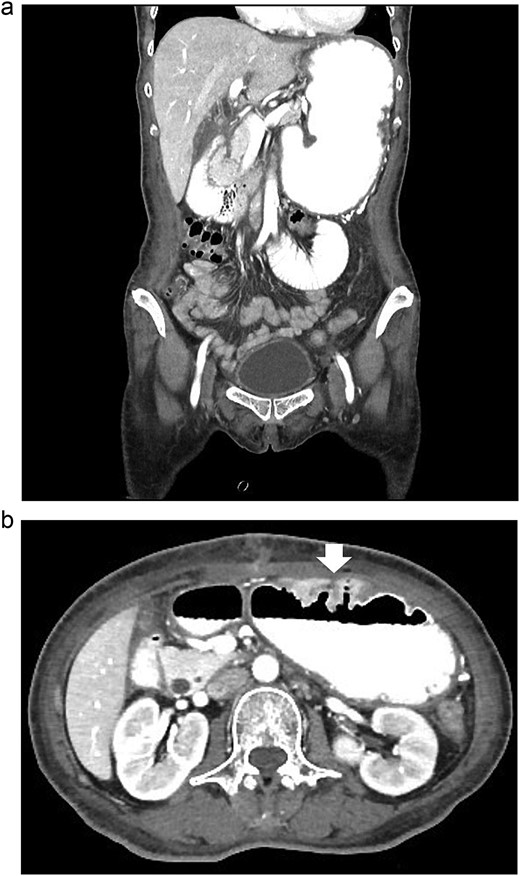

According to these clinical and radiological finding, concern of recurrent gastric outlet obstruction has been raised. Therefore, the computed tomography (CT) scan of the abdomen was performed and showed gastric and afferent limb dilatation, no oral contrast filling in efferent limb and collapsed remaining small bowel loop just distal to gastrojejunostomy anastomosis (Fig. 1). The CT scan findings was afferent limb syndrome associated with efferent limb obstruction due to gastrojejunostomy anastomosis angulation and kinking. The patient was rehydrated with intravenous fluid. Nasogastric tube was placed for decompression. After 5 days of conservative treatment, the abdominal distention was improved but the content from nasogastric tube was continuingly 800–1000 ml per day. Upper endoscopy under general anesthesia was performed for definite diagnosis and chance for endoscopic treatment. It showed patent gastrojejunostomy anastomosis but the both proximal afferent and efferent limb were angulated. Endoscopic dekinking was performed by gentle passage of the endoscope tip across the angulated segment until the intraluminal intestinal segment distal to the obstruction point was reached (Fig. 2).

Upper endoscopic findings: (a) patent gastrojejunostomy anastomosis, (b) afferent limb distal to the angulation, (c) efferent limb distal to the angulation.